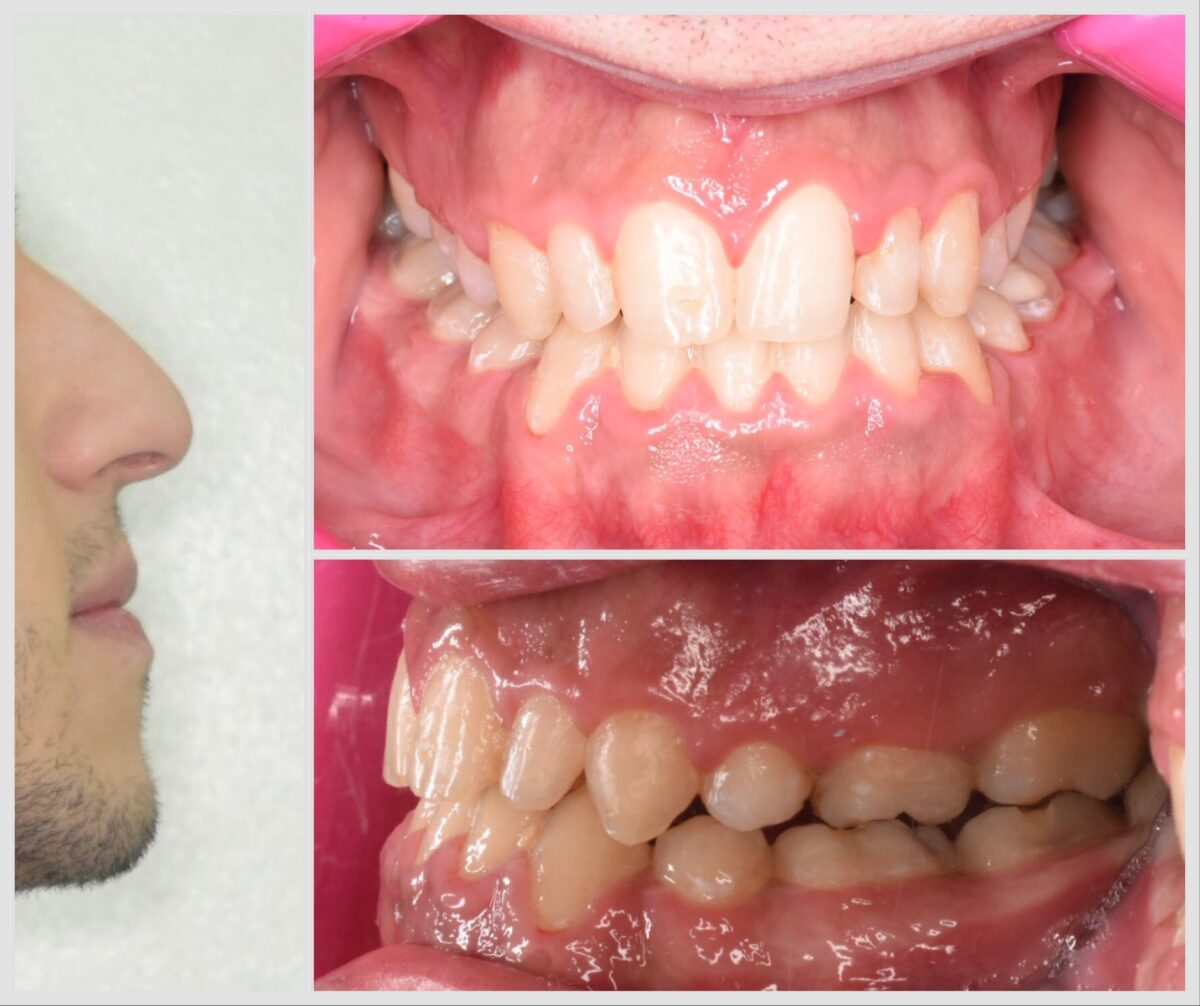

للي محتاجين تقويم، سواء معدني أو شفاف، العيادة بتوفر أحدث حلول التقويم المناسبة لكل حالة، مع متابعة دورية لضمان تقدم العلاج بالشكل المطلوب. وكمان لو في فقدان سن، بيتم تعويضه بزرعات أسنان من التيتانيوم المعتمد دوليًا بعد فحص شامل لعظام الفك وأشعة دقيقة، لضمان أفضل ثبات ونتيجة تدوم سنين.